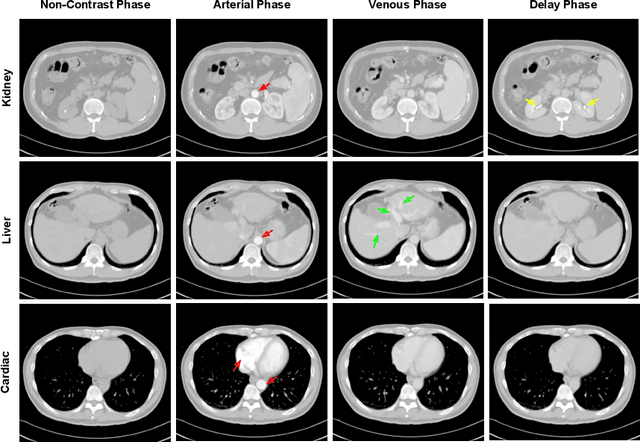

Abstract:As the demand for more descriptive machine learning models grows within medical imaging, bottlenecks due to data paucity will exacerbate. Thus, collecting enough large-scale data will require automated tools to harvest data/label pairs from messy and real-world datasets, such as hospital PACS. This is the focus of our work, where we present a principled data curation tool to extract multi-phase CT liver studies and identify each scan's phase from a real-world and heterogenous hospital PACS dataset. Emulating a typical deployment scenario, we first obtain a set of noisy labels from our institutional partners that are text mined using simple rules from DICOM tags. We train a deep learning system, using a customized and streamlined 3D SE architecture, to identify non-contrast, arterial, venous, and delay phase dynamic CT liver scans, filtering out anything else, including other types of liver contrast studies. To exploit as much training data as possible, we also introduce an aggregated cross entropy loss that can learn from scans only identified as "contrast". Extensive experiments on a dataset of 43K scans of 7680 patient imaging studies demonstrate that our 3DSE architecture, armed with our aggregated loss, can achieve a mean F1 of 0.977 and can correctly harvest up to 92.7% of studies, which significantly outperforms the text-mined and standard-loss approach, and also outperforms other, and more complex, model architectures.